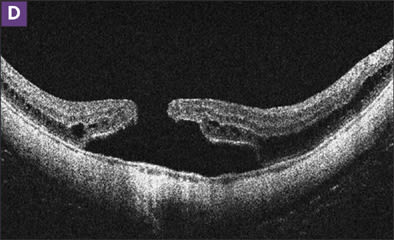

Figure 1. MHRD was repaired by vitrectomy with epiretinal membrane removal and C2F6 gas (A and B). The hole remained closed over 3 years of follow-up (C), although retinoschisis was developing (D). Residual membrane is visible in the nasal macula. Visual acuity improved from 20/400 to 20/40.

Recent attention has been focused on the role of tangential traction in the formation of myopic macular hole. Electron microscopy of surgical specimens shows myofibroblasts on the ILM, and contraction of these cells presumably results in tangential macular traction.15 Attempted removal of epiretinal membranes (ERM) alone does not appear to sufficiently relieve all tangential traction (Figure 1). Chen et al. achieved only a 50% reattachment rate with ERM peeling due to recurrence of membrane formation.16 ILM peeling is thought to be a definitive method of removing all overlying residual vitreous cortex, ERM, and cellular constituents. Complete removal of the ILM may also increase the flexibility of the detached retina that may counter the centrifugal stretching force caused by the posterior staphyloma. Studies in which eyes with MHRD were treated with vitrectomy, ILM peeling, and gas achieved retinal reattachment in over 90% of cases.15,17 Ueomoto et al. reported successful reattachment in 92.3% of eyes in which ILM was peeled vs 50% reattachment in eyes in which ILM was preserved.17 Lam et al. found that ILM peeling increased the odds of retinal reattachment, despite a relatively low overall reattachment rate of 63.2%.18